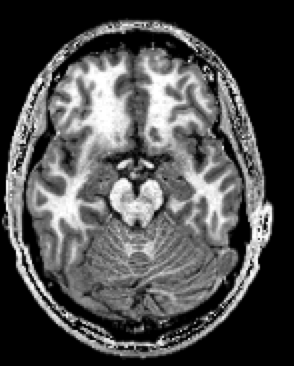

Hi, This happens with all the images in the database. I attach a screenshot of a view of the MRI. Attached is also a screenshot of the process. Sometimes it gets stuck either directly in bias correction or already in the histogram analysis step. Thanks, |

OK, I have seen the image, and actually yes, there is a problem with the bias correction step, which completely fails to determine the region it focuses on. This is due to a signal/noise calculation which compares noise in the center of the image (brain) and near the corner (background). However when the background is completely black (no noise because of a removal of data), then it fails. This is a weakness in Morphologist that we should fix, but hasn't yet. |

There is a simple solution to this problem: add a small gaussian noise to the input data. You can do it using the process in brainvisa: "Tools/misc/Add gaussian noise to data": use the raw T1 MRI as both input and output, and set a s…